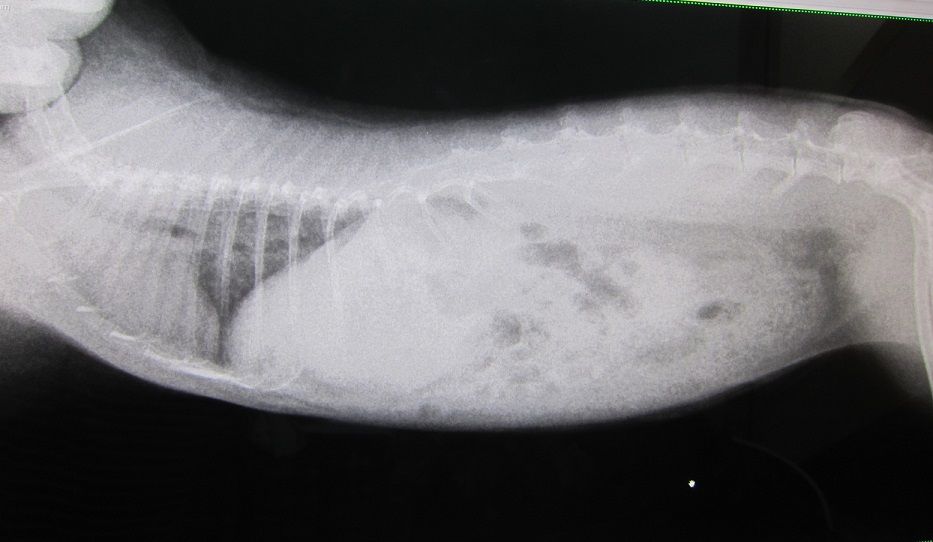

話を戻し、まずは切歯の状態から

臼歯のチェック

処置室でしそびれたということで、診察室で

抜歯した左側、舌に白いのが付着してたので、見当つけた場所を少し触ると膿が出た、と。

左側上の残る1本はかなり奥に位置し、

膿が出たのはそれより手前、歯のないところから。

上なので、左側の涙とも関係してるんだろうな…。